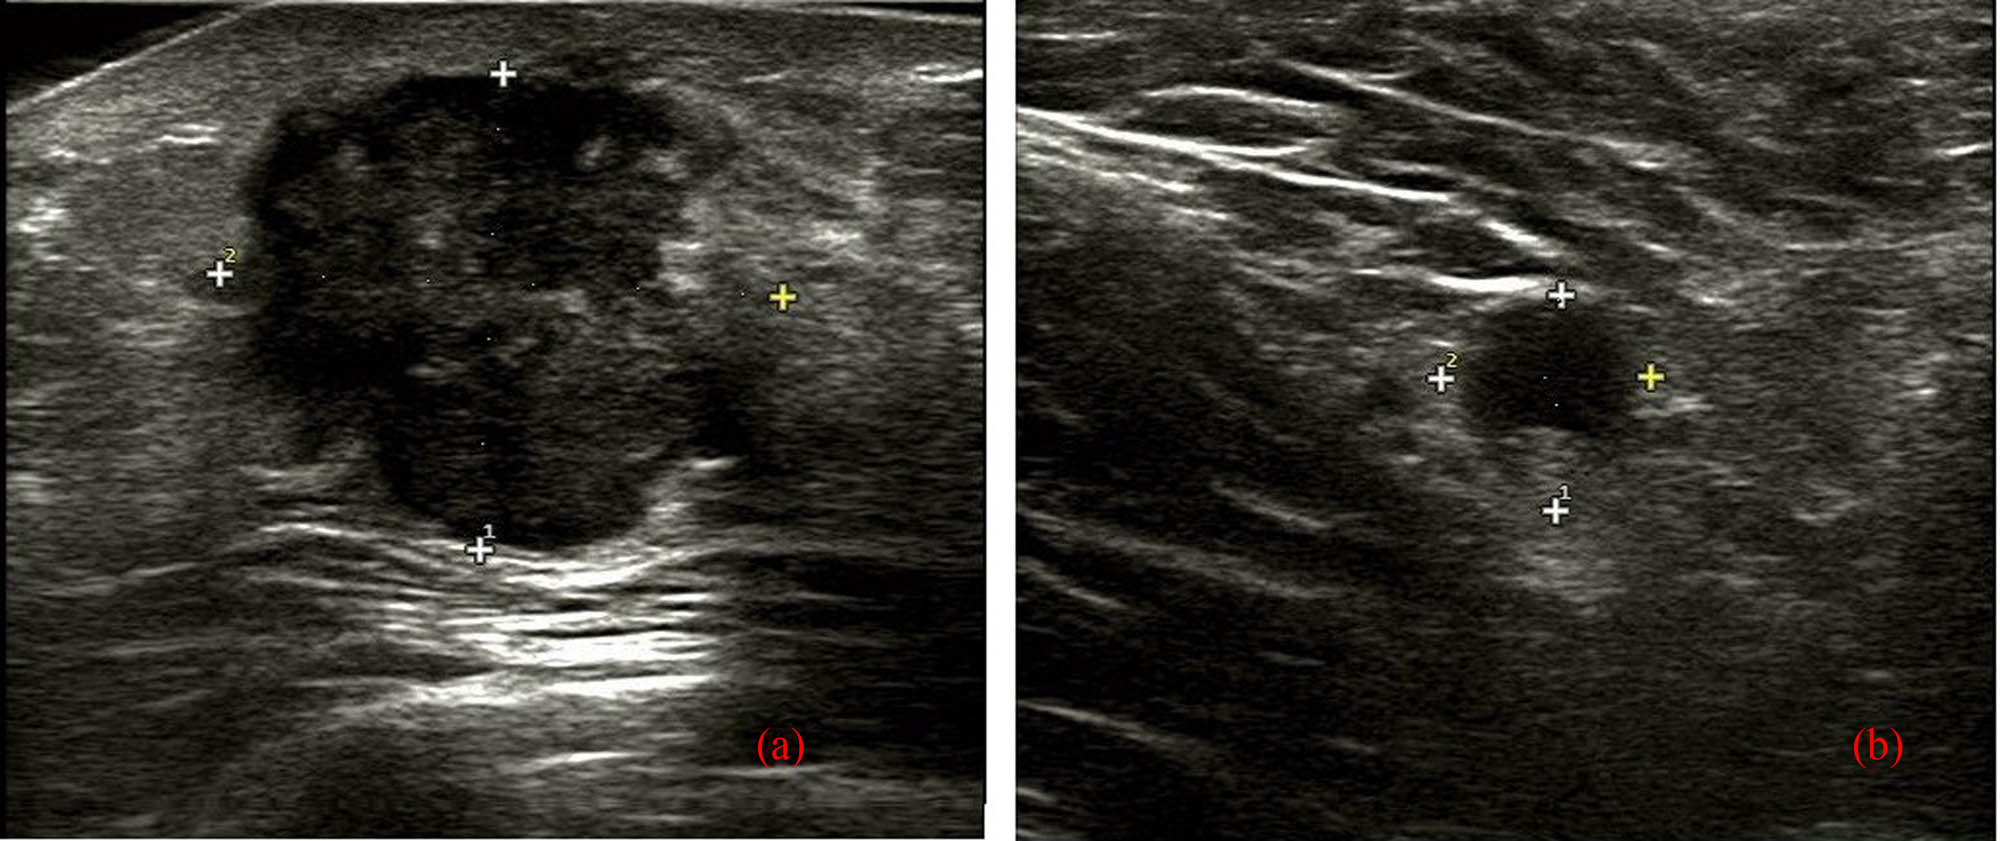

A 52-year-old female was admitted to our hospital with a diagnosis of MBC with osseous differentiation, based on the pathology of the excisional breast mass, without any history of carcinoma or family history of breast cancer. Three months prior, she noticed a mass in her right breast. Physical examination showed a firm, tender mass, approximately 2.5 cm size in the lower outer quarter of the right breast, without a clear boundary. No redness, swelling, pigmentation, or orange peel changes were found on the skin. No invagination, bleeding, or effusion were found in the bilateral nipple. The left breast and the bilateral axillary and supraclavicular lymph nodes were unremarkable. No obvious abnormalities were found in laboratory tests. Breast ultrasound (US) (Figure 1) showed an uneven hypoechoic mass at 9 o’clock near the nipple, and the maximum size was approximately 3.0 cm, with unclear boundary, irregular shape, posterior acoustic enhancement, and few blood flow signals inside. The mass was considered Breast Imaging Reporting and Data System (BI-RADS) category 4A, and a suspected enlarged lymph node with a slightly thickened cortical area at the right axillary region was also indicated by US.

US of MBC with osseous differentiation. US revealed that there was an uneven hypoechoic mass at 9 o’clock near the nipple, with unclear boundary, irregular shape, and posterior acoustic enhancement, and few blood flow signals inside, but without definite calcifications (a) and the suspected enlarged lymph node with a slightly thickened cortical area at the right axillary region (b).